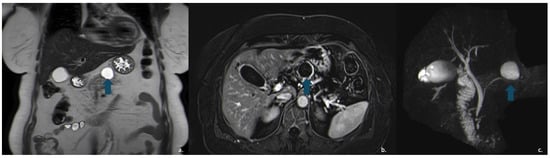

Figure 10.

The same patient as in Figure 7 underwent Contrast-Enhanced MRI, which showed a lesion (arrow) with inhomogeneous signal in the T2w—HASTE sequences (a) and areas of restricted diffusion in DWI and ADC maps corresponding to the mural nodules. (b,c) The patient subsequently underwent surgical resection, and histopathology confirmed a degenerated mucinous cystadenoma.